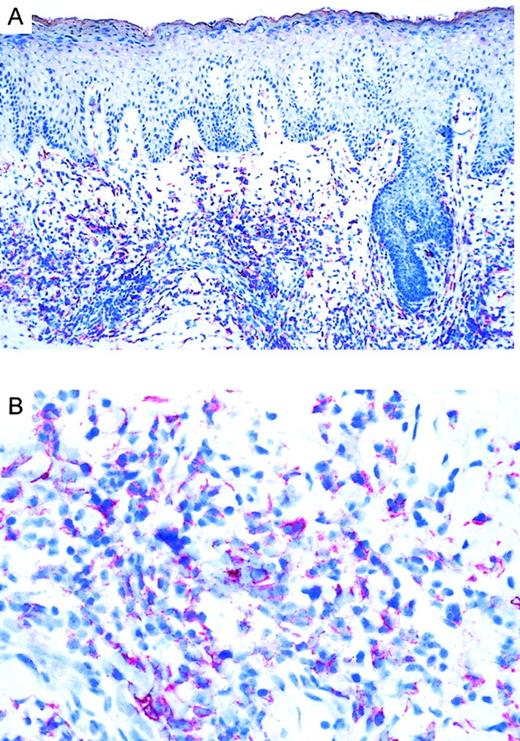

Twenty CTCLs, consisting of 8 CD30+ large-cell lymphoma, 6 mycosis fungoides, and 6 Sézary syndrome patient samples, were analyzed by immunohistochemistry. CD30 was expressed in all large-cell CTCLs (Table 1). Variation in the admixture of inflammatory cells accounted for the difference in numbers of CD30+ cells in the infiltrate. Staining for the chemokine receptor CCR3 demonstrated expression of CCR3 in 7 of 8 CD30+ CTCLs investigated (Table 1; Figure1). No epidermotropism of CCR-3+ cells was observed. There was faint staining of keratinocytes, which is explained by the recently described CCR3 expression on these cells.21 Mycosis fungoides (n = 6) and Sézary syndrome (n = 6) sections were CD30−except one case (no. 17) where few CD30+ cells were detected. In CD30− CTCL, there were always fewer than 5% of cells positive for CCR-3. In most cases, the extent of CD30 expression corresponded to the expression of CCR3 (Table 1). CCR4 expression was found in 4 of 8 CD30+ CTCLs as well as 1 of 6 MF cases and 1 of 6 Sézary syndrome cases. No CCR8 staining was observed in any of the samples.

Immunoreactivity of CCR3 in CTCL.

(A) CCR3 immunoreactivity in cryosections of a CD30+large-cell CTCL (no. 7) with the use of the alkaline phosphatase/anti–alkaline phosphatase method. Original magnification, × 100. (B) CCR3 immunoreactivity in cryosection of a CD30+ large-cell CTCL (no. 7) with the use of the alkaline phosphatase/anti–alkaline phosphatase method. Original magnification, × 400.

To confirm our immunohistochemistry data on a single-cell level and to assess expression levels of CCR3 on CD30+ lymphoma cells, we performed flow cytometric analysis of tumor cell suspensions. Tumor cells suspensions were derived from fresh biopsy material, which was available in 3 patients with CD30+ large-cell CTCL (nos. 1, 7, and 8). Cells were double-stained for CCR3 and CD30 and analyzed by flow cytometry. Compared with isotype control, a strong coexpression of the chemokine receptor CCR3 and CD30 was detected (Figure 2; patient no. 7). Strong staining in immunohistochemistry (Figure 1) translated into a high level of CCR3 expression on CD30+ tumor cells in flow cytometric analysis (Figure 2; patient no. 7). The majority of CD30+ cells were CCR3+. Expression levels were comparable to those seen in eosinophils (data not shown).